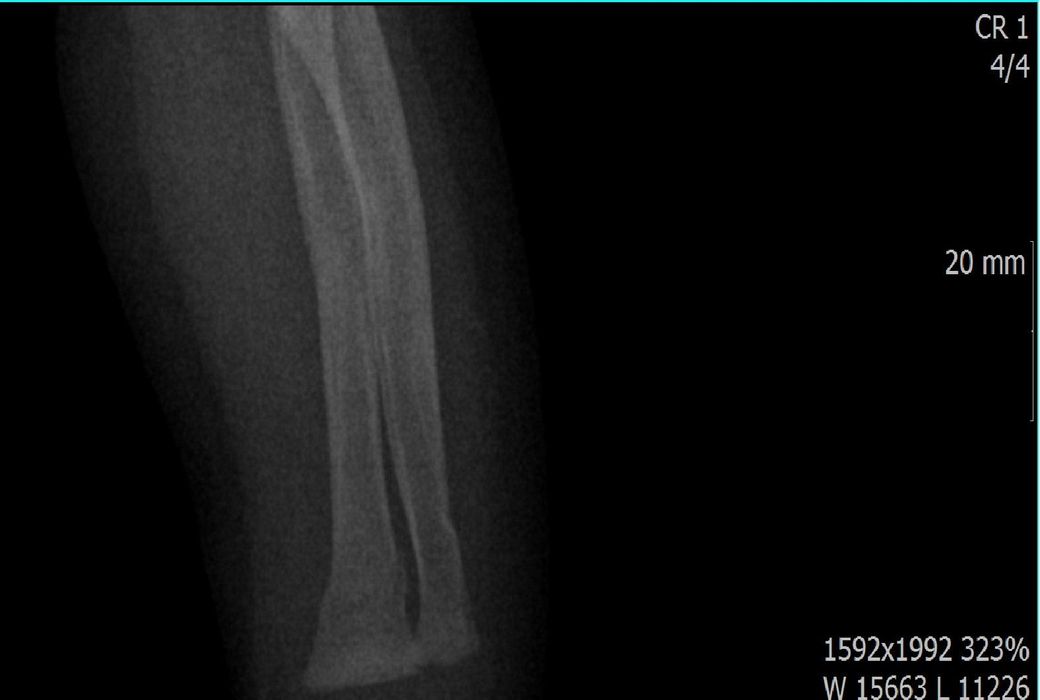

다름이 아니라, 첨부드린 엑스레이(X-ray) 사진처럼 골절 사실을 알게 되고 골절 발생 시점 대략적으로나마 추정시기를 파악하려고 문의 드리게 되었습니다

1) 3월 30일 촬영한 X-ray만으로 정확한 골절 시기를 100% 특정하는 데에는 한계가 있다는 점 충분히 인지하고 있기에 촬영날짜 기준으로 대략적으로 어느정도 시점에서 발생되었을 것으로 추측(ex 당일, 7~10일전, 7~14일 전, 10일 ~ 20일전, 14일 ~ 30일전 등등등)되는지 이해하고 싶습니다.

첨부드린 파일에는 없지만 4월 5일 사진에서는 캘로스 라는 것이 발견된다고 합니다.

• 2번 째 사진